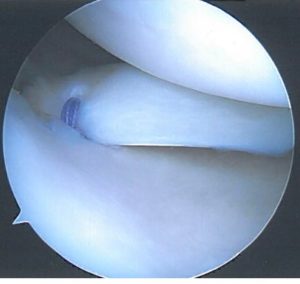

Επίσης σε αποσπαστικη ρήξη ρίζας οπισθίου κέρατος μηνίσκου ( meniscal root tear) σε σχετικά νέα άτομα γίνεται αρθροσκοπική συρραφή και σταθεροποίηση.

Στις πλείστες όμως περιπτώσεις που η ρήξη του μηνίσκου είναι κεντρικότερα, στις περιοχές αυτές η αιμάτωση είναι ελλιπής και τότε αντιμετωπίζεται με μερική μηνισκεκτομή δηλαδή αφαιρείται τμήμα του ρηθέντος μηνίσκου με προσπάθεια να διατηρηθεί το μεγαλύτερο μέρος του μηνίσκου ακέραιο.